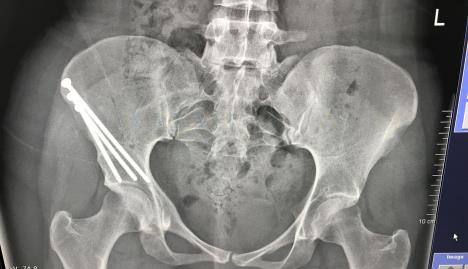

Rendgenski snimak Kamilinog stanja Foto: Jam Press / Jam Press / Profimedia

Na kraju mi je dijagnostikovao nekoliko različitih problema sa kukovima koji su izazivali moj bol, od kojih su najznačajniji bili displazija kuka, sindrom hipermobilnosti zglobova i retroverzija acetabule.

U proteklih 10 godina, Kamila je imala pet operacija kako bi pomogla sa simptomima, uključujući rekonstrukciju kuka.